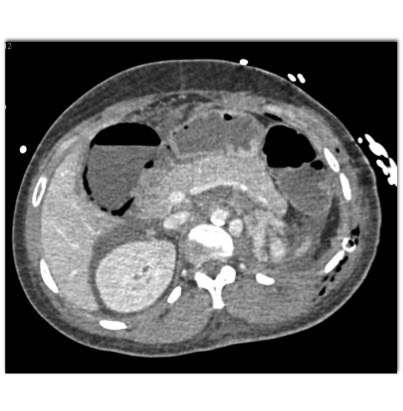

In this patient the most likely diagnosis for the new liver lesions is?

liver abscess

liver infarcts

metastases to the liver

focal fatty infiltration